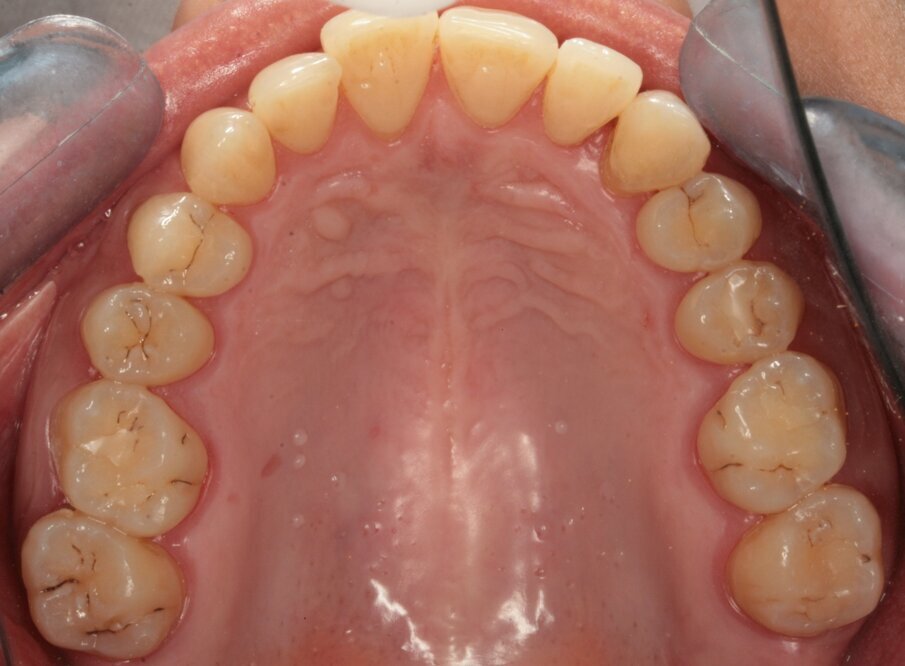

La paziente, FF di anni 38, è giunta alla mia osservazione per la cura delle lesioni cariose presenti. All’esame obiettivo non erano evidenti lesioni cariose di notevole entità (Figg. 1, 2): solo attraverso le bite-wing (Figg. 3, 4), mezzo indispensabile per la diagnosi odontoiatrica in conservativa, si evince la presenza di numerose lesioni cariose coinvolgenti il tessuto dentinale. La paziente richiedeva il raggiungimento di un risultato estetico ottimale, ovvero la mimetizzazione del materiale composito con il tessuto smalteo; oltre a questa esigenza si doveva unire quella di effettuare una riabilitazione funzionale ovvero, trattandosi del settore posteriore, che sopportasse il carico masticatorio garantendo la minima usura possibile nel tempo. Alla paziente è stato proposto un piano di trattamento che prevedeva la cura diretta delle lesioni cariose suddivise per quadranti e la riabilitazione indiretta dell’elemento 47 in modo da permettere la migliore precisione marginale garantendo un ottimo follow-up a lungo termine. Si è proceduto con la riabilitazione mediante il composito di recente introduzione Enamel Plus HRi Bio Function (Micerium, Avegno, Genova). Bio Function è disponibile in 3 smalti: BF1 basso valore - BF2 medio valore - BF3 alto valore e in 9 dentine: BD0 - BD0,5 (per restauri di denti particolarmente bianchi o sbiancati) BD1 (A1 Scala Vita) - BD2 (A2 Scala Vita) - BD3 (A3 Scala Vita) - BD3,5 (A3,5 Scala Vita) - BD4 (A4 Scala Vita) BD5 - BD6.

Fig.1_Visione occlusale dell’arcata superiore.